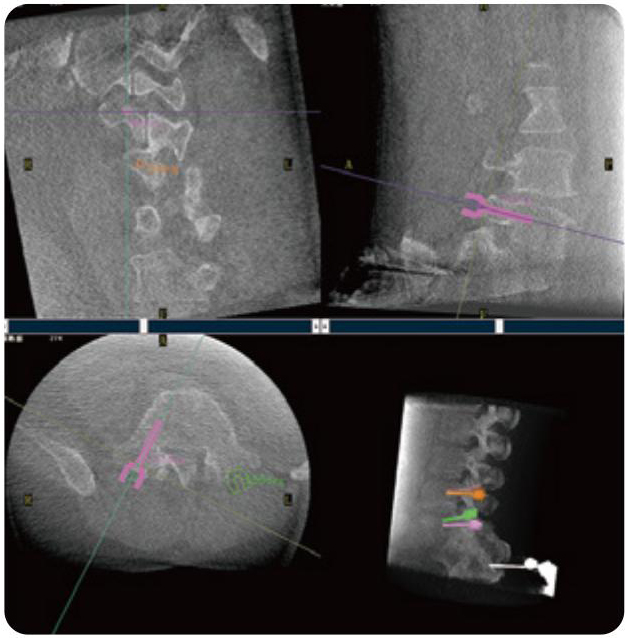

PL300B可應用于多節段脊柱外科手術,輔助醫生定位病灶部位,為脊柱外科手術(經皮椎體成形術、椎弓根螺釘內固定術等術式)提供術前手術流程規劃、入釘位置、角度可視化引導,模擬仿真入釘輔助。

PL300B搭配普愛醫療自主研發生產的平板3D C形臂,借助一體化自適應配準( 軌跡配準)技術,通過追蹤C形臂三維采集軌跡,自動完成圖像坐標建立和系統坐標配準。配準精度更高,操作步驟少,系統運作效率高。